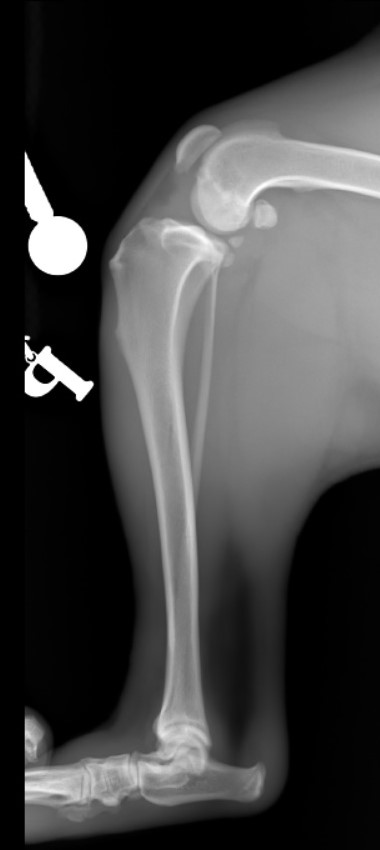

Nazywam się JJ :) Nigdy nie sądziłem, że będę potrzebował Waszej pomocy. Mam dopiero rok, urodziłem się 14 kwietnia 2019 roku. Lubię biegać, popiardywać, walczyć z odkurzaczem i dawać buziaczki człowiekom. Moi kochani opiekunowie przygarnęli takiego klopsa jakim jestem (a raczej byłem) ja... Mając zaledwie 4 miesiące zachorowałem na parwowirozę. Moje człowieki zrobili i oddali wszystko co mogli dać, abym wyzdrowiał. I tak się stało! Jednak zacząłem chorować bardzo szybko i po cichutku. Zaczęły boleć mnie moje tylnie nogi. Starałem się biegać, ale moje kolanka za bardzo bolały, więc ograniczyłem używania tylnich nóg do minimum podczas biegania. Żeby wejść na kanapę muszę bardzo się wysilić lub prosić moich człowieków, aby mi pomogli. Nie jestem w stanie wejść ani zejść po schodach bez odpoczynku. Moi kochani bracia i siostry (bo jesteśmy liczną rodzinką) patrzą na mnie z przykrością... Moje nietypowe siadanie na boku zaciekawiło domowników. Musiałem stworzyłem sobie garb, aby odciążyć nogi. Później pojawiły mi się guzki na prawej i lewej nodze. Na lewej nóżce guzek był troszkę większy, więc od razu pojechaliśmy do weterynarza. Niedobrze, bo guzki były już troszkę duże... Zapalenie, a może początek raka. Moja nowa Pani weterynarz zaczęła podejrzewać dysplazję biodrową. To mogłoby wyjaśnić moje “dziwaczne” siedzenie. Jednak nie była pewna, więc wysłała nas do specjalistów. Tam zrobili mi zdjęcia rentgenowskie i trochę mnie powyciągali. Bardzo mnie to bolało. Czułem wszystko, pomimo Jasia, którego dostałem. WERDYKT: Ześlizg główek w kościach kolana lewego i prawego o 33%, a to podobno bardzo dużo. Moje guzki to skutek rozlanego płynu zapalnego w kolanach. Moje lewe kolano choruje bardziej niż prawe. Jak się okazało nie urodziłem się z tym, ani nie jest to genetyczne. Po prostu zachorowałem na to. Moje kochane człowieki dostały dwie opcje.